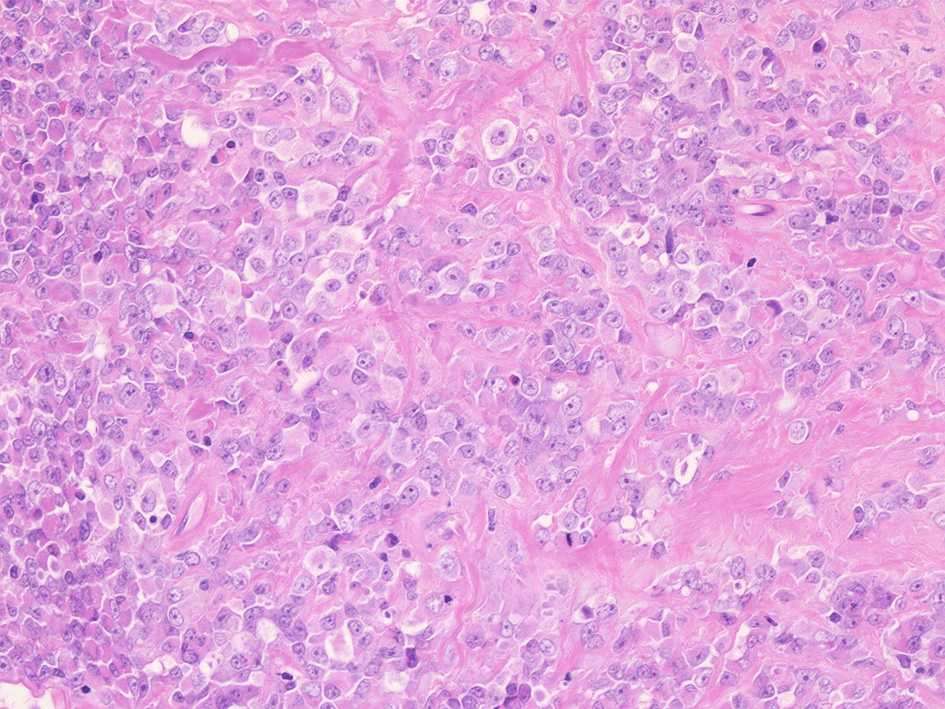

壁側胸膜腫瘤切除標本 病理組織所見

部分的に細胞接着性が低く疎な組織像を呈する.

① rhabdoid cellsが密に増殖する組織像. 核は類円形vesicularで, 中心性の大型核小体を1個もつ. 細胞質は好酸性.

球状の封入体様にみえる構造が出現し, 核偏在や核を圧排し, 三日月/半月状の核がみられている. mitosisが散在. 形質細胞が少数混在して認められる.

② 少量の線維性組織を間質に類円形/多稜形のvesicularな核と好酸性, 淡明な細胞質をもつ類上皮様の中~大型の細胞が集簇, 増殖している.mitosisが多い. 辺縁にはrhabdoid cellsのchohesiveな増殖が認められる.

③ 間質の線維組織が多く, 硝子化やmyxomatous changeが認められる. 二核の大型巨細胞が散在している. 細胞は比較的一様なサイズ形態で, 多型は高度ではない印象.